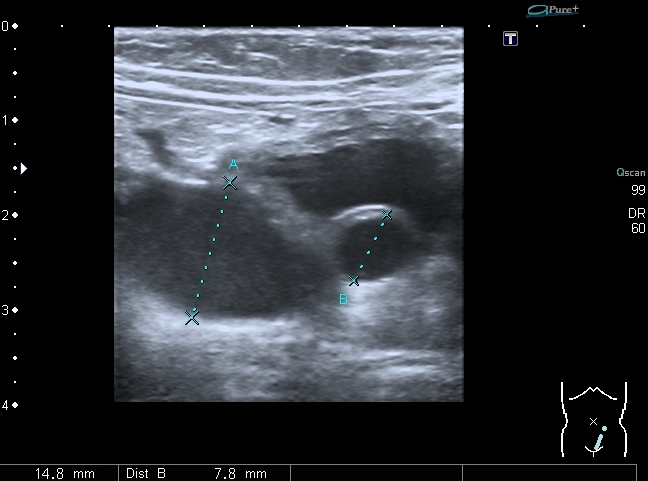

В мочевом пузыре определяется достаточно большое уретероцеле слева, периодически увеличивающееся и пульсационное уретероцеле справа. Левый мочеточник в нижней трети резко расширен.

Назвал данную тему именно так потому-что меня заинтересовали два момента:

1. Толстая стенка у левого уретероцеле .

2. Транзиторность ( пульсационность, периодичность, непостоянство

не знаю , как красивее назвать) уретероцеле справа.

ЧЛС и проксимальный мочеточник справа не расширен, правой почки на сканах нет, поскольку с её стороны ничего плохого я не заметил. Появилась мысль посмотреть на всё это на фоне введения диуретика - м.б. появится расширение собирательной системы справа